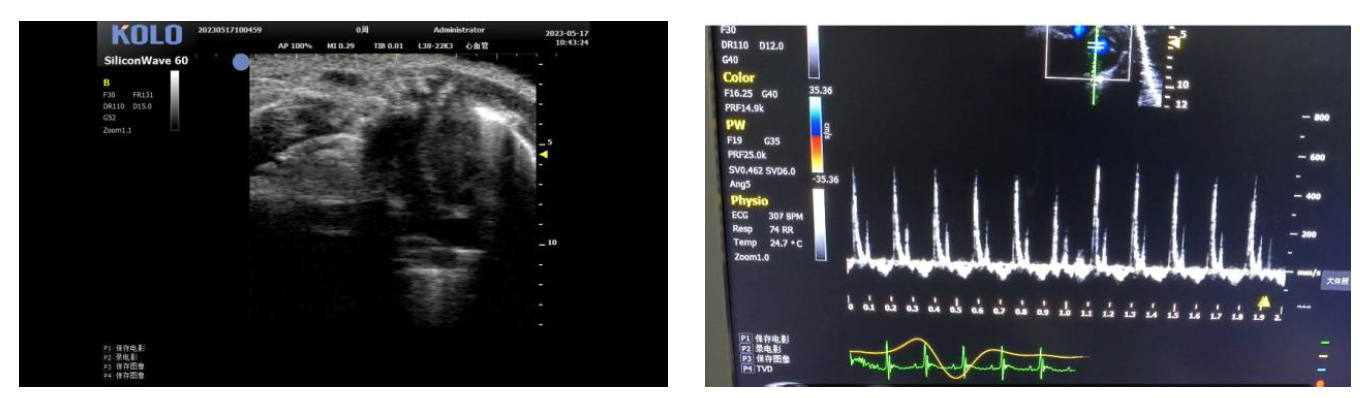

3、小鼠血管方面研究

3.1 腹主动脉(长+短轴+管壁距离测量+血流流速)

3.2 颈动脉(长轴)